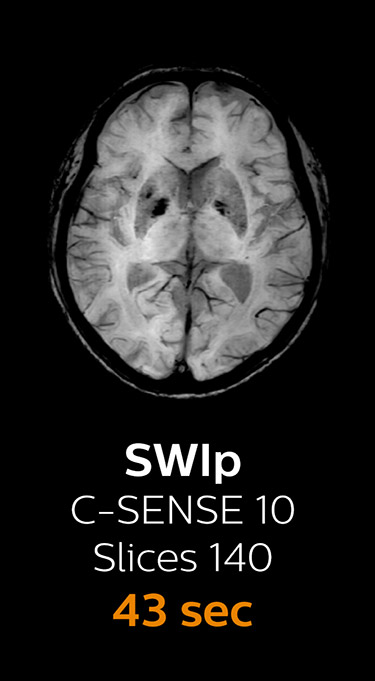

“We now only need about 10 minutes of scan time for a brain exam – and we still get the same amount of images and equal quality. We even managed to make a very useful improvement: we replaced the 43-second T21 FFE by a 43-second SWIp, which is more powerful for us in making confident diagnoses in certain patients.” “SWIp was not previously included in our standard protocol, because of its slightly longer scan time. SWIp provides high resolution 3D susceptibility weighted imaging in the brain, which helps to visualize small deoxygenated blood or calcium deposits. Now, with Compressed SENSE, we can perform 3D SWIp in only 43 seconds, so we have included SWIp instead of the 2D T21 FFE that we used previously. Without adding scan time, we now get SWIp images in every routine brain scan and it helps us increase our diagnostic confidence in certain cases.”

The most frequently used brain MRI examination at KNC included approximately 15 minutes of scanning time, and was quite comprehensive with fairly short scan times. When Compressed SENSE became available, its great impact on the brain exam quickly became clear.

Fast MRI of brain

With Compressed SENSE, the scan time for the routine brain examination at KNC was reduced from 15:48 to 10:19 minutes, which corresponds to 35% reduction.

Ingenia 3.0T CX

Scan time 15:48 min.

Brain with Compressed SENSE

Ingenia 3.0T CX

Scan time 10:19 min.